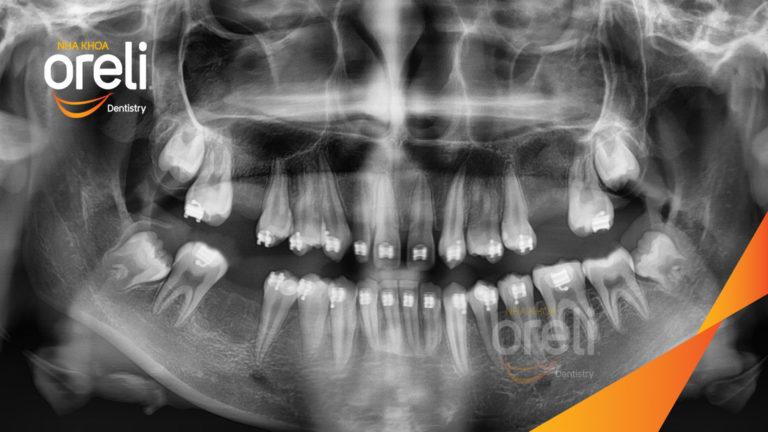

Tháo mắc cài ca niềng răng sai khớp cắn hạng 3 không nhổ răng tại Oreli

Ca niềng răng sai khớp cắn hạng 3, cắn chéo chen chúc răng cửa, mất răng 6 hàm dưới, răng…